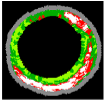

K-means, FCM, and Self-Organising Maps (SOM) algorithms have been adapted for VH-IVUS image segmentation. The adapted algorithms are then implemented in Matlab software. A comparative study between the applied clustering methods was conducted using 86 images obtained from three patients. Figure 8 depicts the average of SW for Patient 1 (11 images), Patient 2 (42 images), and Patient 5 (33 images) by applying the FCM, K-means, and SOM algorithms. Horizontal and vertical axes indicate the frame number of the VH-IVUS image and the average of Silhouette Weight (SW), respectively.

Figure 8.

The average SW obtained by FCM, K-means, and SOM algorithms for Patients 1, 2, and 5.

As shown in Figure 8, the best result was obtained by the K-means algorithm, while the worst result was obtained by applying the SOM algorithm. In addition, the results of FCM algorithm for Patients 1, 2, and 3 were more than 0.92, indicating that this algorithm can be applied for VH-IVUS segmentation. Additionally, the VH-IVUS data obtained from 10 patients were divided into training and testing datasets. Frames provided by patient 1 were considered the training set, and the rest were defined as the testing set. FCMPSO-mED, KMPSO-mED, HFCM-mED, and HFCM-kNN [45] models were implemented in MATLAB R2014b software (The Mathworks, Inc., Natick, MA, USA). Figure 9 illustrates the comparison of KMPSO-mED and HFCM-mED.

Figure 9.

Comparison of KMPSO-mED, HFCM-mED for 10 Patients.

Regarding Figure 9, FCMPSO-mED achieved a greater SW than HFCM-mED for Patients 3 and 4, while HFCM-mED achieved better results for Patients 2 and 6. The two methods obtained the same results for the other patients. Figure 10 illustrates the comparison of SW achieved by the FCMPSO-mED, KMPSO-mED, and HFCM-kNN models.